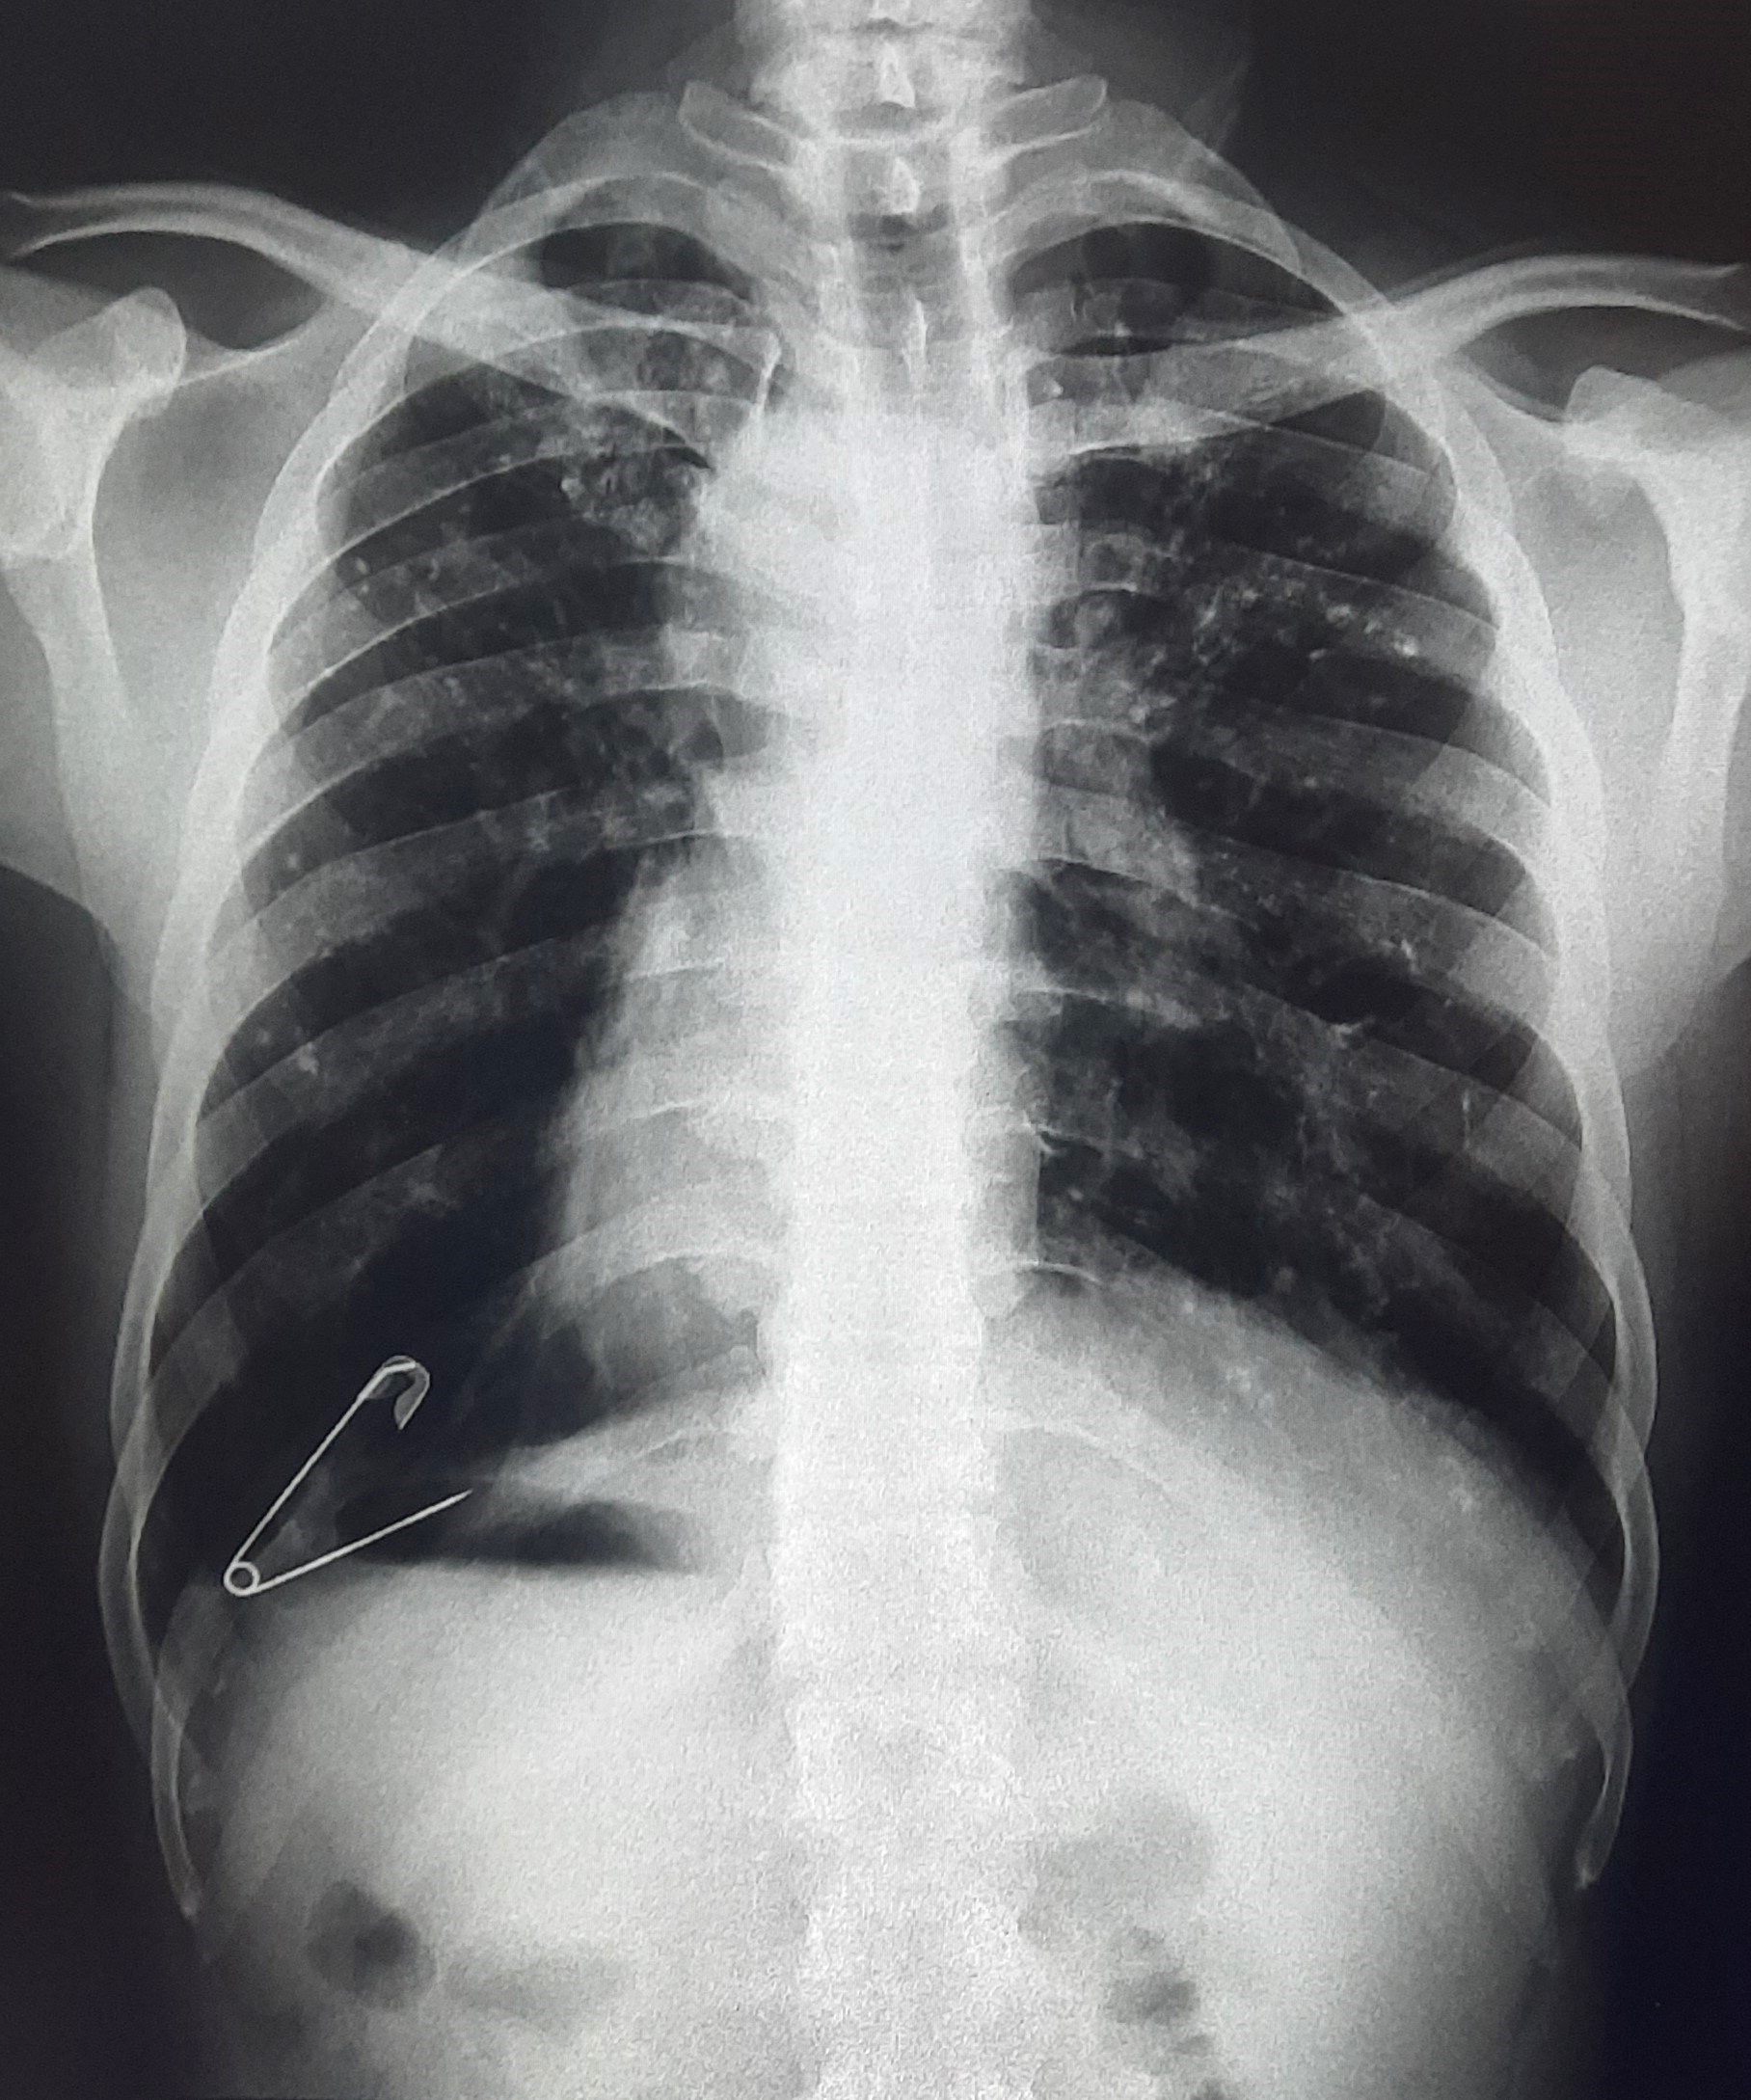

| 101 | IGGMC, Nagpur, Nagpur | P2 | 29-4371 | Ajihul Hag | Consent taken on Paper | 76 Yrs. |

Provisional Diag : Right sided Pleural effusion

Final Diag : Right Sided Loculated Pleural Effusion (CxR- Microbiologically Confirmed PTB With Clinically diagnosed Right sided Pleural effusion) |

TB Case (Confirmed) | Right Sided CP Angle Blunting, Right Lower Zone Homogenous Opacity Present | Abnormality visible on x-ray |